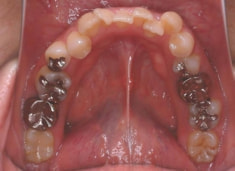

治療後(2年5ヶ月後)

治療開始から約1年2ヶ月後